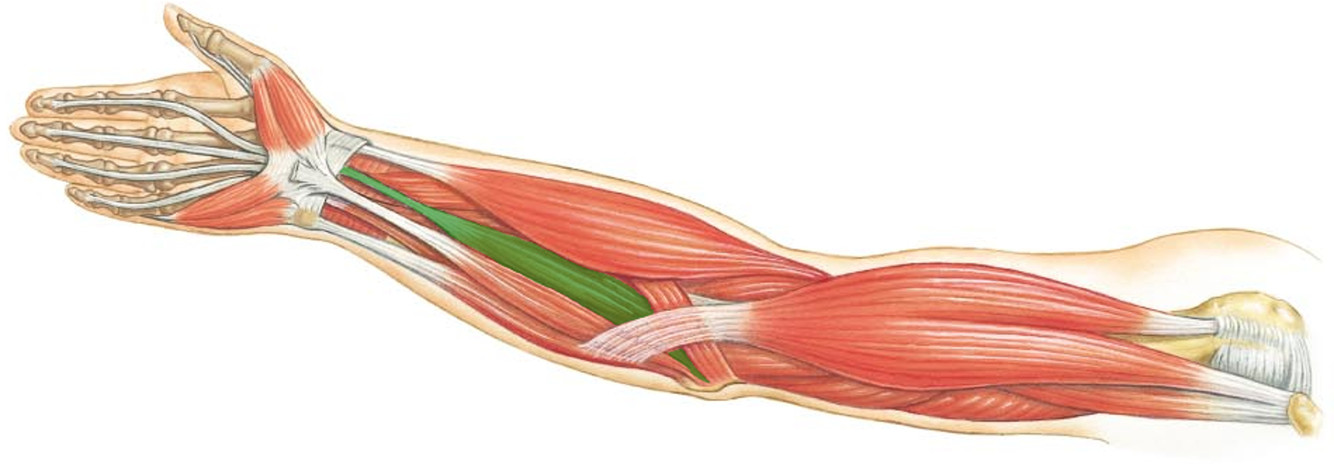

What is the innervation of this muscle?

Muscle - Flexor pollicus longus

Median nerve

C8 + T1

What is the innervation of this muscle?

Muscle - Flexor carpi radialis

Median nerve

What is the innervation of this muscle?

Muscle - Palmaris longus

Median nerve

What is the innervation of this muscle?

Muscle - Flexor digitorum superficialis

Median nerve

C7 - T1